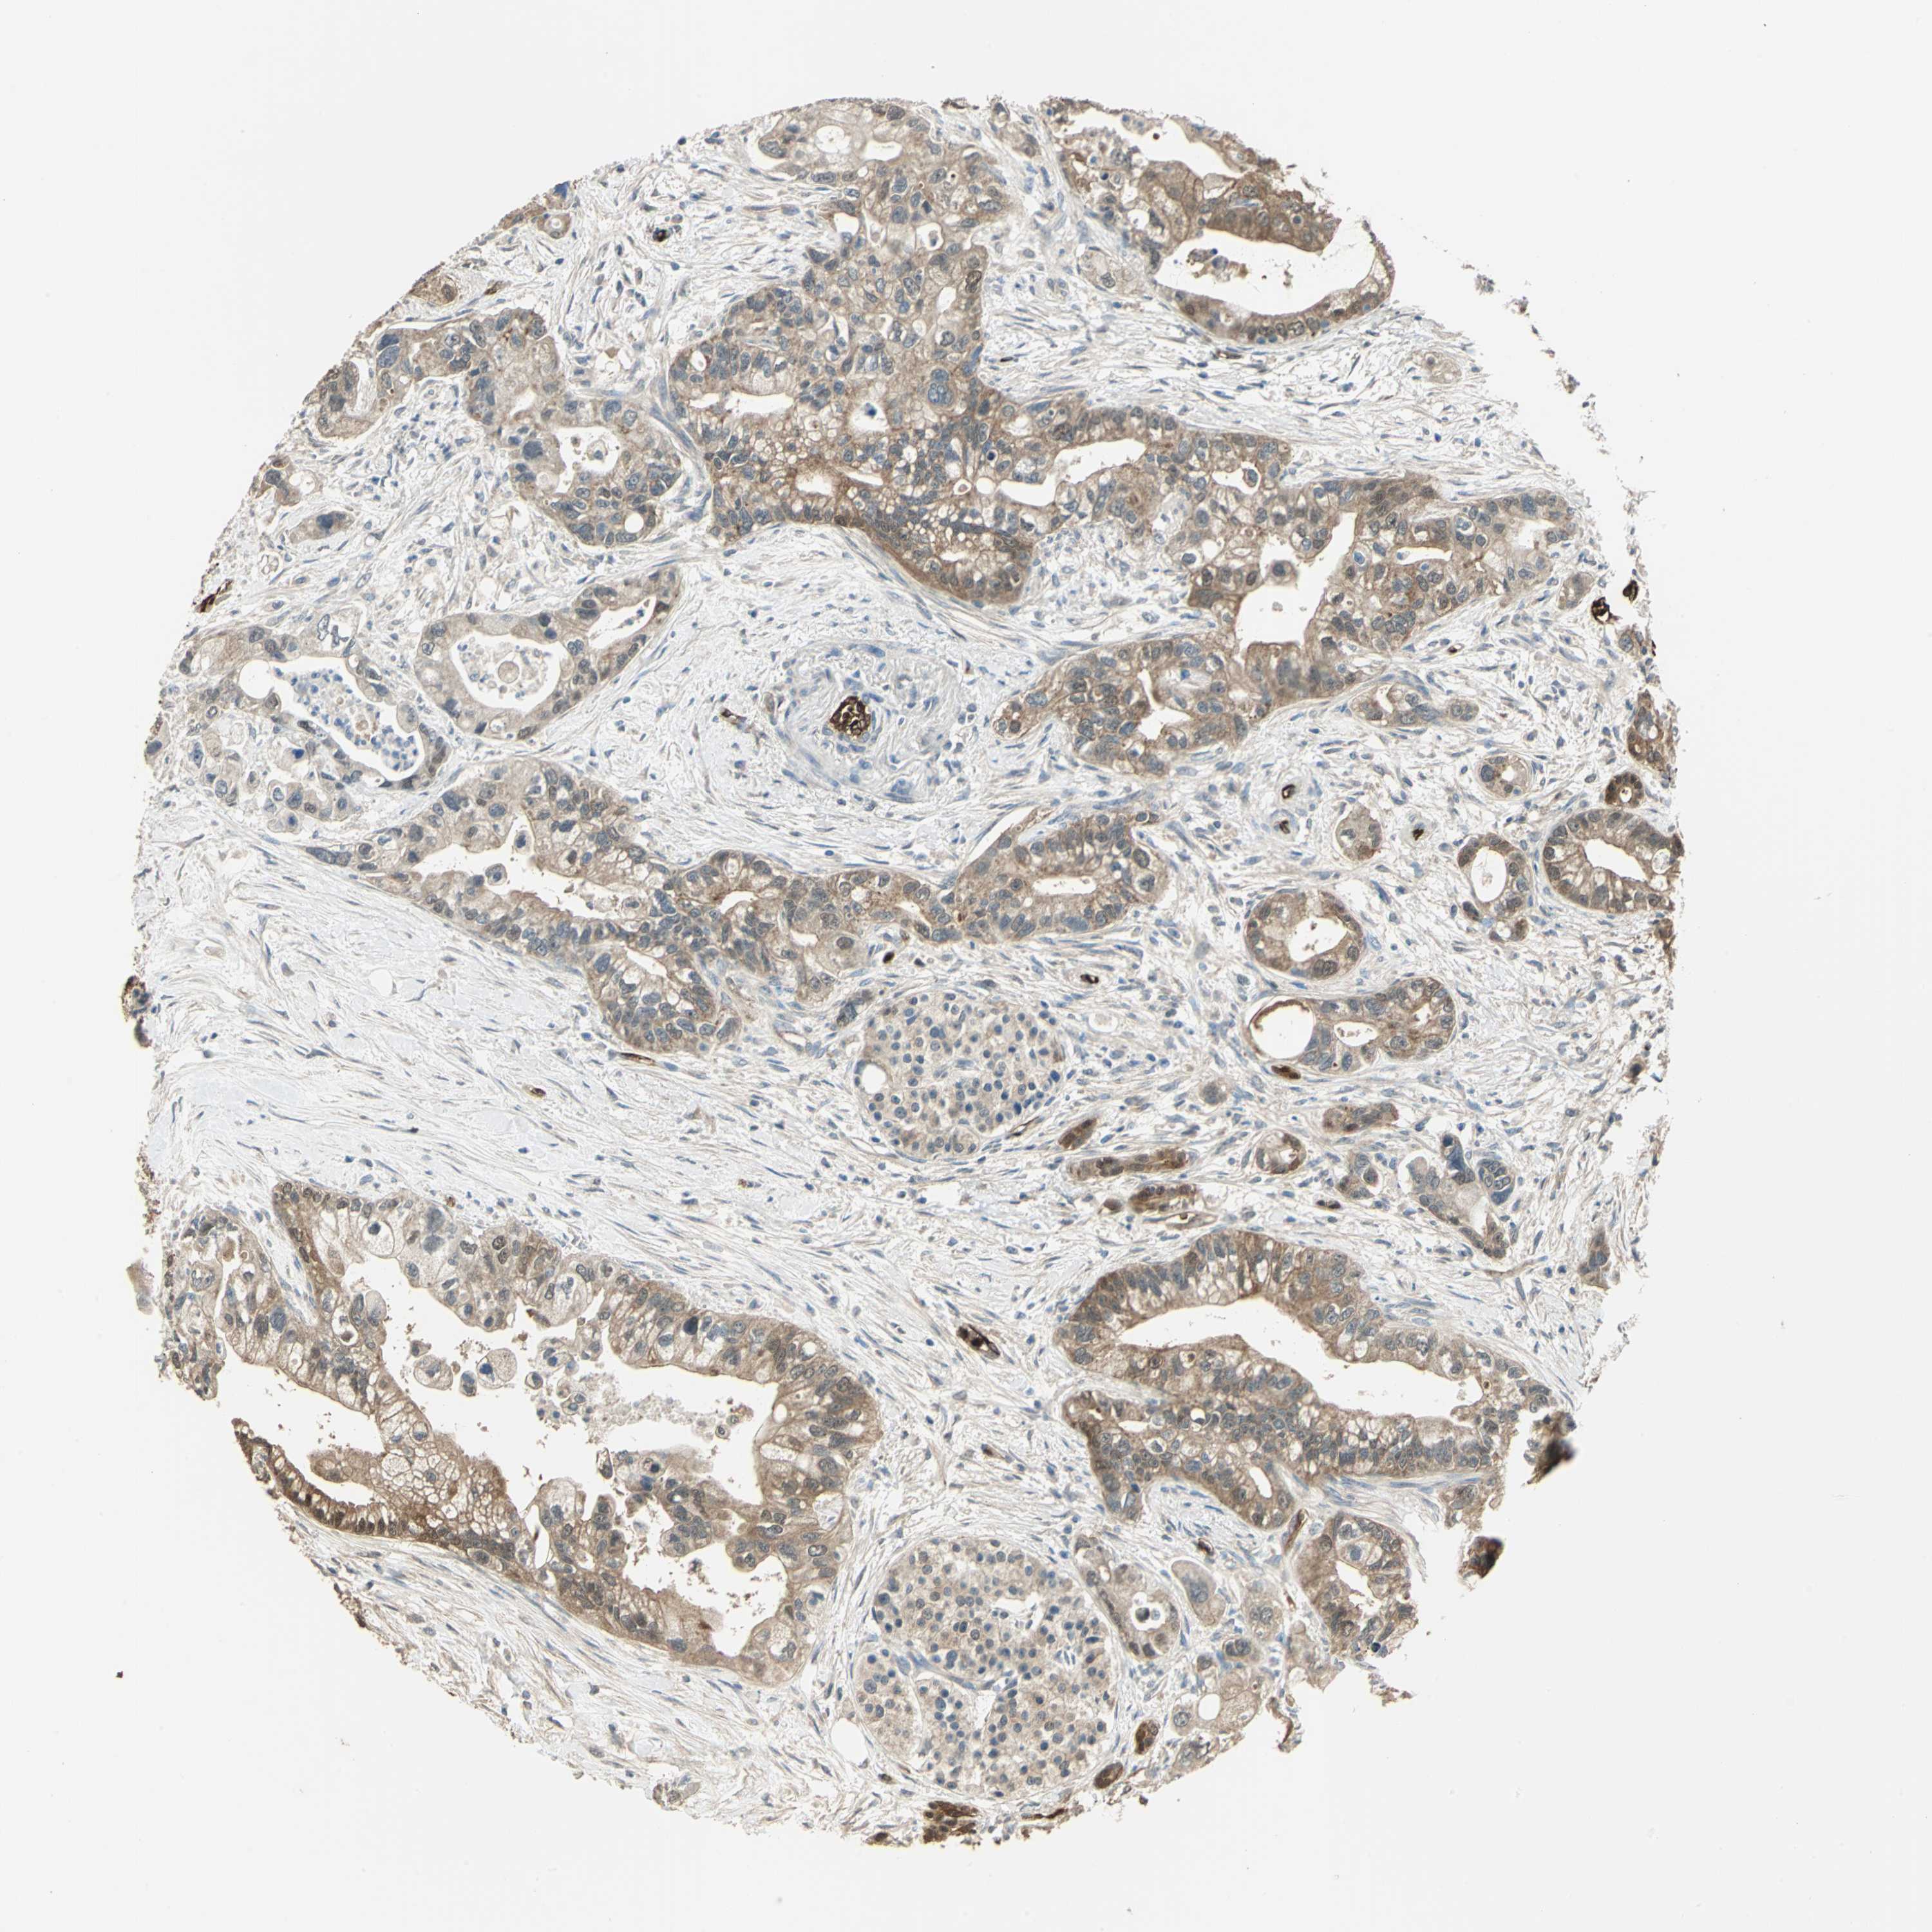

PANCREATIC CANCER - Protein expressioni

A mouse-over function shows sample information and annotation data. Click on an image to view it in a full screen mode. Samples can be filtered based on level of antibody staining by selecting one or several of the following categories: high, medium, low and not detected. The assay and annotation is described here.

Note that samples used for immunohistochemistry by the Human Protein Atlas do not correspond to samples in the TCGA dataset.

Antibody stainingi

Antibody staining in the annotated cell types in the current human tissue is reported as not detected, low, medium, or high, based on conventional immunohistochemistry profiling in selected tissues. This score is based on the combination of the staining intensity and fraction of stained cells.

Each image is clickable and will lead to virtual microscopy that enables deeper exploration of all samples and also displays staining intensity scores, fraction scores and subcellular localization as well as patient and tissue information for each sample.

Antibody HPA006308

Antibody HPA071064

Staining

High

Medium

Low

Not detected

Intensity

Strong

Moderate

Weak

Negative

Quantity

>75%

75%-25%

<25%

None

Location

Nuclear

Cytoplasmic/membranous

Cytoplasmic/membranous,nuclear

Adenocarcinoma, NOS

Adenocarcinoma, metastatic, NOS